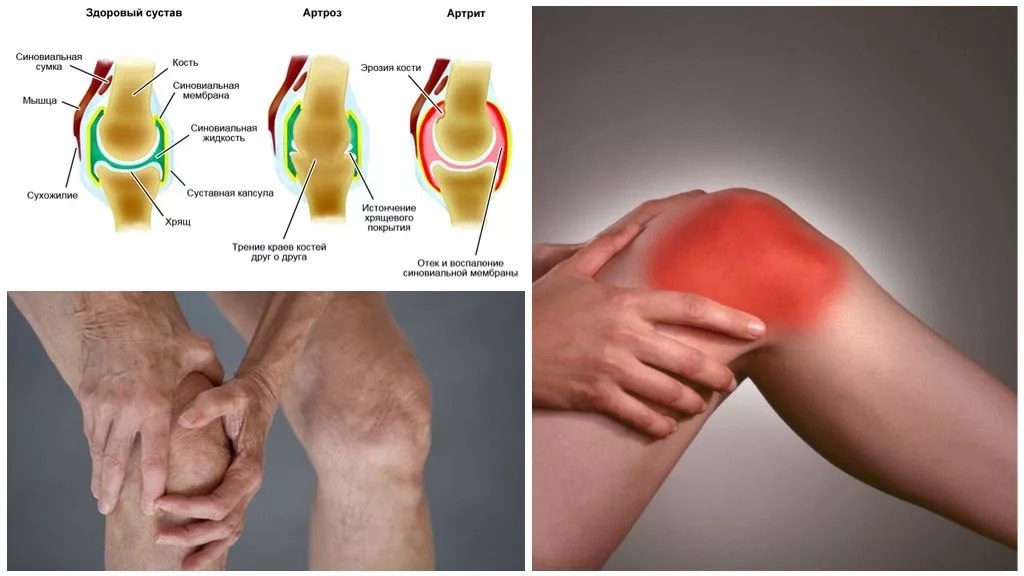

Медицинские состояния: Септический артрит коленного сустава